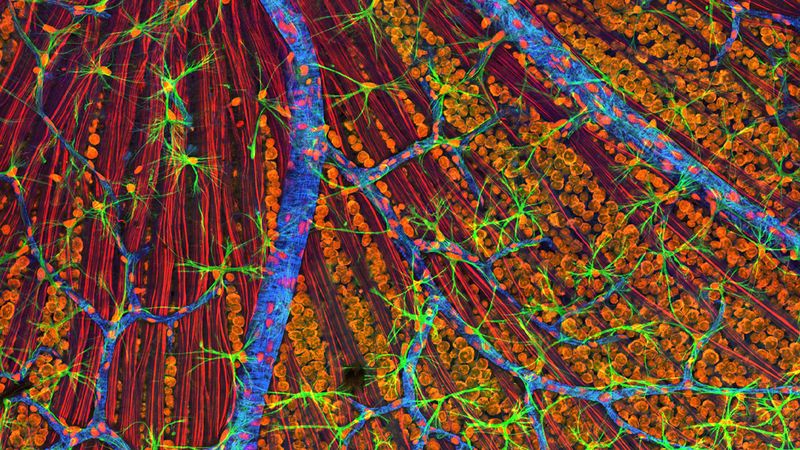

The patient was assessed and found to have difficulties with memory, verbal memory, and had a tendency to conflate two stories into one. Using cognitive tests and scans of his brain, the team found signs of Alzheimer's Disease.